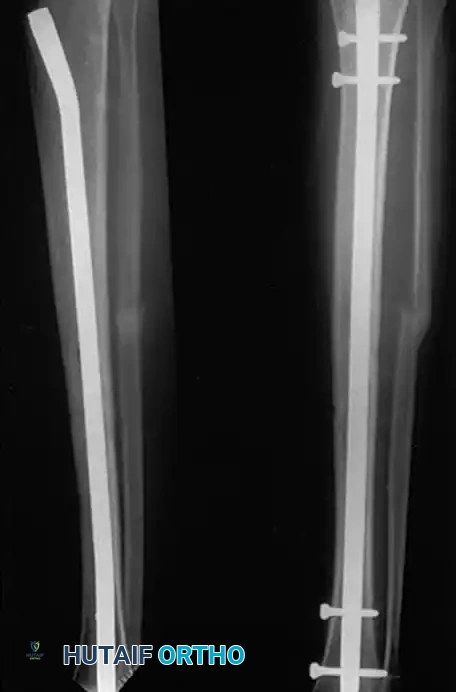

Intramedullary Nailing vs. Casting

Locked intramedullary (IM) nailing is currently the preferred treatment for most diaphyseal tibial shaft fractures requiring operative fixation.

Bone et al. retrospectively compared IM nailing and cast treatment for isolated displaced tibial shaft fractures. Nonunions occurred in only 2% of nailed fractures compared to 10% of casted fractures. Furthermore, 10% of casted fractures healed with unacceptable malalignment, whereas none of the nailed fractures did. Puno et al. and Hooper et al. corroborated these findings in prospective trials, demonstrating superior union rates, lower malunion rates, and faster return to work with IM nailing.

Associated Surgical & Radiographic Imaging